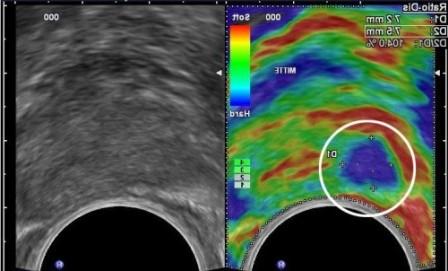

УЗИ с эластографией дает возможность поставить пациенту точный диагноз, не прибегая к такому болезненному методу, как биопсия. К тому же, если введение иглы с целью изъятия кусочка тканей для морфологического исследования в область молочной железы просто болезненно, то биопсия почек несет большую угрозу здоровью и жизни человека.